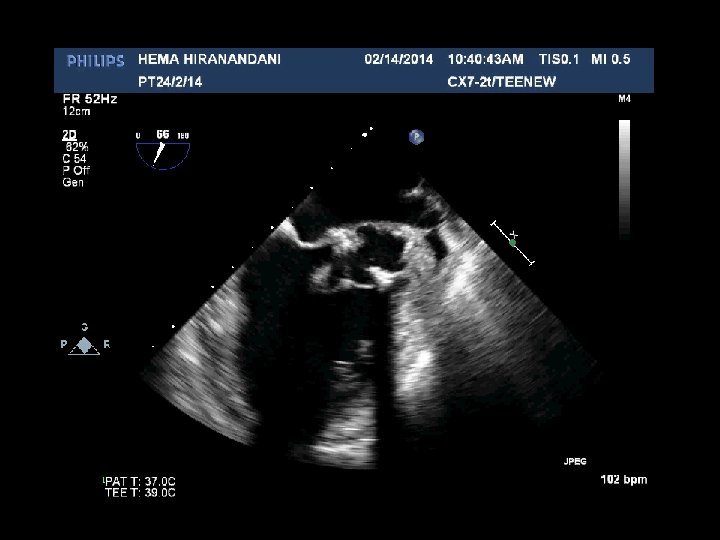

HEMA HIRANANDANI F 57 YRS • • • AVR BIO PROSTHETIC VALVE DEHISCENCE IE MULTIPLE VEGETATIONS ON BIO PRO VALVE AO ROOT ABSCESS SEVERE PARAVALVULAR AR RVSP= 37 mmhg

Hema Hirandani